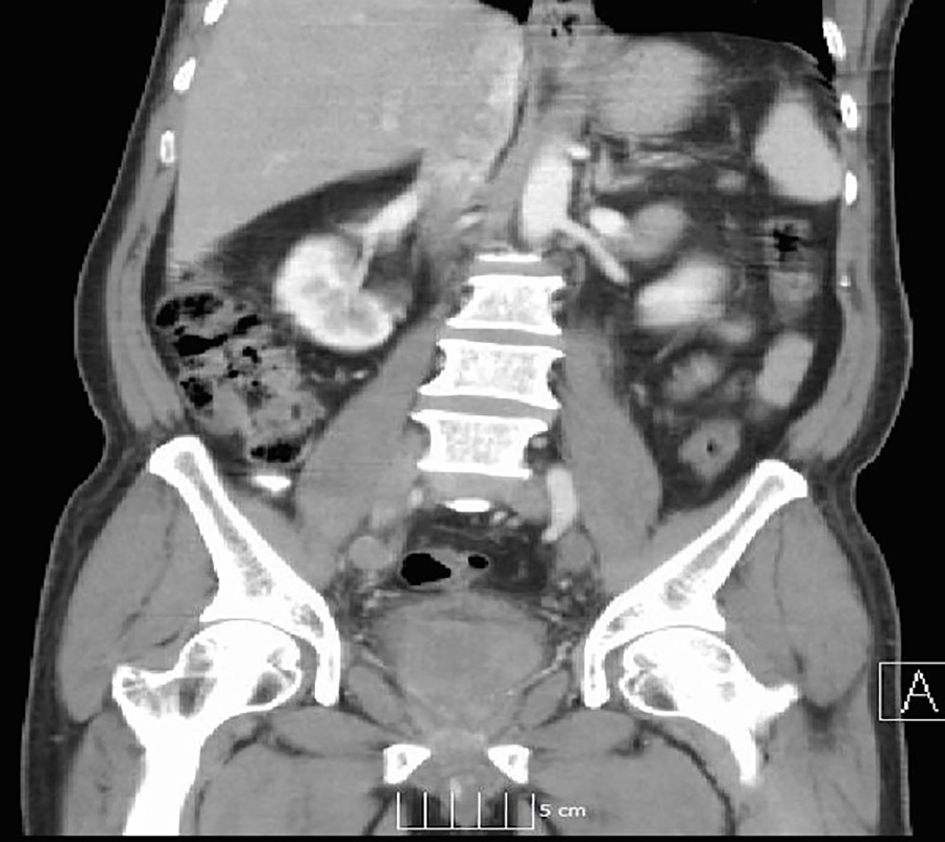

A 49-year-old man, current smoker, with past surgical history of cholecystectomy, presented with several weeks history of difficulty in urination, as well as dysuria, pelvic pain and occasional hematuria, with subjective fever. He had been treated with tamsulosin and finasteride as an outpatient with minimal relief. Due to persistent pelvic pain and obstructive uropathy, he was admitted to the hospital. On initial evaluation, patient was noticed to have mild suprapubic tenderness and no costovertebral angle tenderness or urethral discharge. Routine laboratory tests were within normal limits except hemoglobin 11.6, prostate-specific antigen (PSA) 0.4 ng/mL and lactate dehydrogenase (LDH) 347. Computerized tomography (CT) scan showed a 7 × 4 cm lobulated mass below the base of the bladder, possibly arising from the superior aspect of the prostate and invading the seminal vesicles. There was right pelvic/inguinal adenopathy with largest node measuring 2 cm posterior to the external iliac vessels and no evidence of distant metastatic disease (Fig. 1). This was further investigated by a prostate biopsy which revealed prostatic tissue with diffuse involvement of sheets of atypical cells with large irregular nuclei, prominent nucleoli numerous mitotic figures with immunohistochemical stains showing the tumor cells positive for CD45+, CD20+, BCL2+, MUM1+, while negative for CD10, BCL6, cyclin-D1, PSA, CK903, and P504S, consistent with diagnosis of a diffuse large B-cell lymphoma (DLBCL), activated B-cell type (Figs. 2 and 3). Bone marrow aspirate and biopsy were normal. Our patient was diagnosed with stage IIE bulky NHL of the prostate with low-intermediate risk group as per NCCN-IPI score. He had a normal echocardiogram and negative hepatitis panel. The patient was subsequently started on chemotherapy with R-CHOP (rituximab, cyclophosphamide, doxorubicin, vincristine and prednisone) regimen. Patient symptoms improved with chemotherapy. After completing six cycles of chemotherapy, patient had a positron emission tomography (PET) scan reporting no hypermetabolic disease and remains in remission and will be followed up closely.

![]() Click for large image | Figure 1. A 7 × 4 cm lobulated mass below the base of the bladder, arising from the superior aspect of the prostate and invading the seminal vesicles. |

In our case, patient presented with obstructive uropathy symptoms and was initially treated with tamsulosin and finasteride for BPH with a poor therapeutic response culminating in further evaluation with imaging, and ultimately tissue biopsy. CT scan revealed prostatic mass with right inguinal lymphadenopathy. Based on the prostate biopsy results and no evidence of distant metastases found, with no bone marrow involvement, we made diagnosis of primary NHL of the prostate (stage IIE).